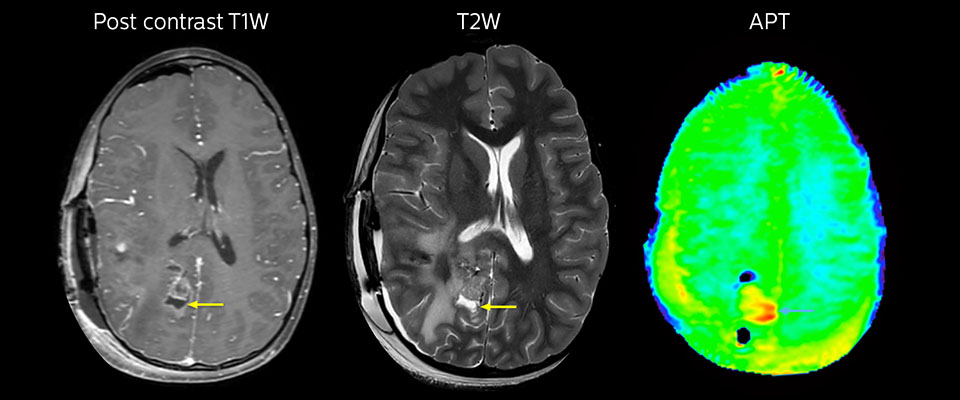

APT may illuminate post-resection images with crucial information

MRI may be performed after tumor resection, to look for residual tumor or tumor regrowth. Also here, the different contrast mechanism of APT may help in diagnosis. Dr. Miller remembers a particular case.

“After a very good resection, we saw small changes on the postcontrast T1-weighted and the T2-weighted images that looked like a post-surgical little bit of fluid. Interestingly, however, we saw a focal area of APT signal, right in the center of that abnormality. As we usually do when a bit unsure, we followed it up and, unfortunately, found tumor regrowth in that region,” Dr. Miller says. “Cases like this motivate me, and others who care about this population, to investigate how this APT method could be used on large scale in this population and help us in providing high value diagnostic information.”

The hospital’s physicians also saw a case where APT had a negative predictive value. Following the resection of a highgrade tumor, they saw a similar small change in the images of this patient. However in this case, the APT signal was rather low. In a recent rescanning of this patient, no recurrence was seen.